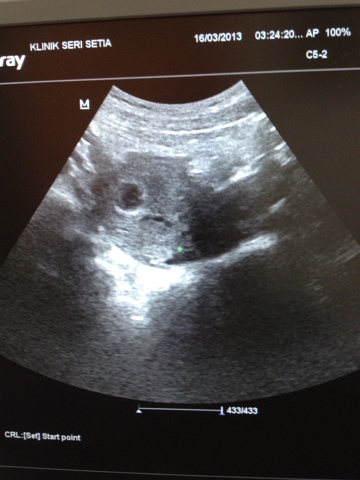

Time mula2 doctor scan perot, aqeef mcm xrela, meronta2 nk mama tapi lepas doctor tunjuk baby adik, ckp2 ngan dia terus ok... ^_^... Alhamdulillah baby adik sehat tapi still sgt kecil dlm tummy mama, Insyaallah due pada 4 November nanti, hujung tahun la plk kali ni. Kakak i ckp nape xsabo tggu skit je lagi, aqeef pon besar skit.. Huhu nk buat mcm mne rezeki Allah nk bagi tahun ni hehe terima dgn hati terbuka =)

| Membesar dengan sehat ye sayang...=) |